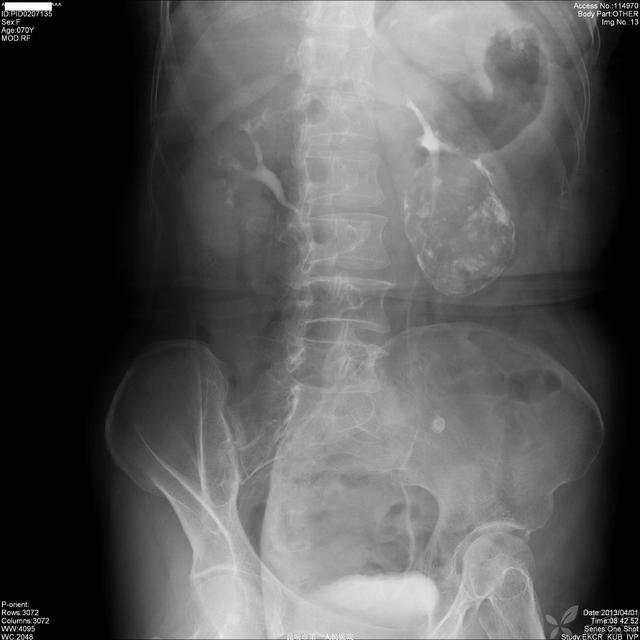

图2,IVU:

img

X线:左肾下极肿块,边界光滑,多发点片状钙化灶,左肾下肾盏受压移位、拉长、变形,肾盂输尿管上段未受侵犯。